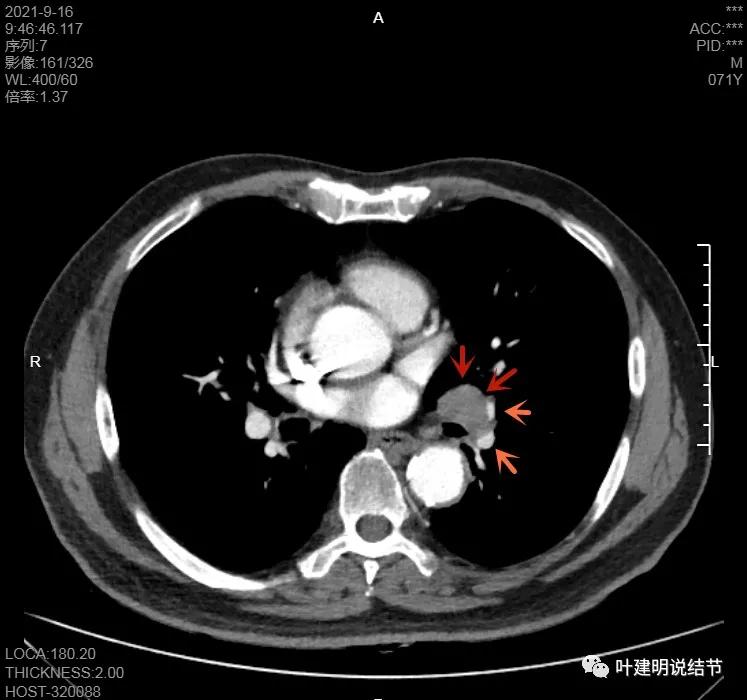

左肺门区淋巴结肿大

肺门区淋巴结挤压附近肺血管,但似乎示见肿瘤侵犯破坏血管壁

淋巴结巨大,部分包绕肺血管,但仍未见明显侵犯血管壁

肺血管受压明显,气管内壁感觉也是光滑的

以上诸图均示肿大淋巴结挤压肺血管,但未见确切侵犯破坏,支气管内壁也感觉是光滑的,没有肿瘤突向管腔